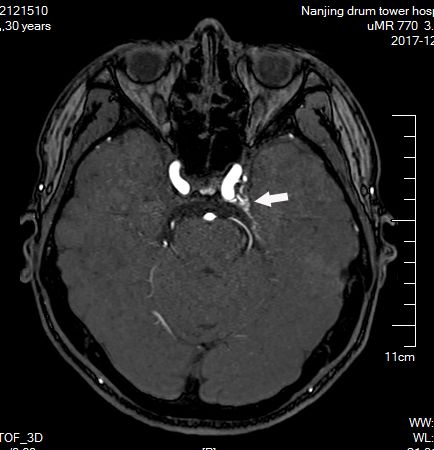

头颅MRA未见颅内异常血管,但头颅MRI-TOF像可见左侧天幕缘异常血管影(图2),CT薄层增强扫描见枕骨大孔区异常血管影(图3)。于2017年12月25日局麻下行全脑及全脊髓血管造影,脊髓血管造影未见异常,双侧椎动脉造影未见异常,最后行左侧颈内动脉造影示脑膜垂体干供血的天幕区硬脑膜动静脉瘘,瘘口位于岩骨中内1/3,直接经桥脑中脑侧静脉、扩张的延髓周围静脉向脊髓前静脉引流(图4)。造影诊断:左侧天幕区硬脑膜动静脉瘘。

图2. MRA未见异常,MRI-TOF示左侧天幕缘异常血管影(箭头所示)